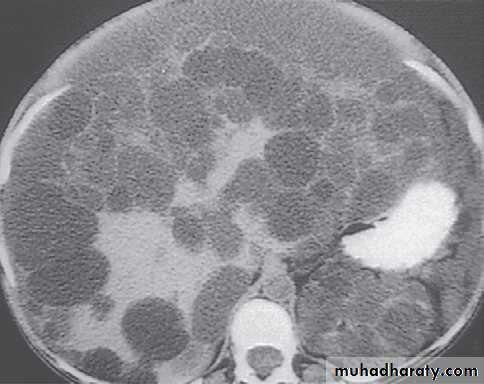

polycystic liver disease. A, a very large, cyst. B several large cysts. C, multiple smaller cysts